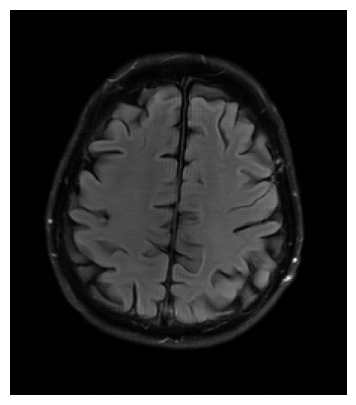

The visual inspection of the images reconstructed (available in Fig. 2) at acceleration factor 4 shows little to no visible difference with the ground truth original image. However, when increasing the acceleration factor to 8, we can see that smoothing starts to appear which leads to a loss of structure as can be seen in Fig. 3.

| T1 PSNR: 41.56 SSIM: 0.9506 | T2 PSNR: 40.68 SSIM: 0.9554 | FLAIR PSNR: 39.60 SSIM: 0.9321 | T1POST PSNR: 42.53 SSIM: 0.9683 |